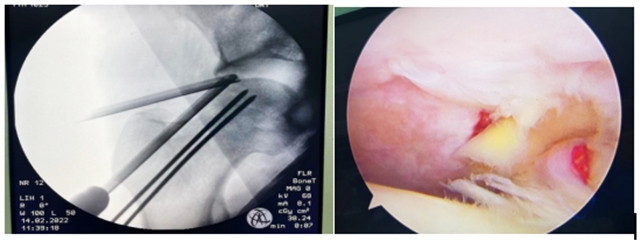

“郝教授,我不想做股骨头置换手术……”郝琦副教授总结十年股骨头坏死临床病例,不断探索股骨头坏死保髋治疗新方案,为王先生制定了髋关节镜清理+钻孔减压治疗。

通过关节镜清除股骨头外关节囊内坏死组织、探查修复受损组织同时囊内减压,再结合钻孔骨内减压,从而改善血供,最终使“死”掉的股骨头重新“活”过来。